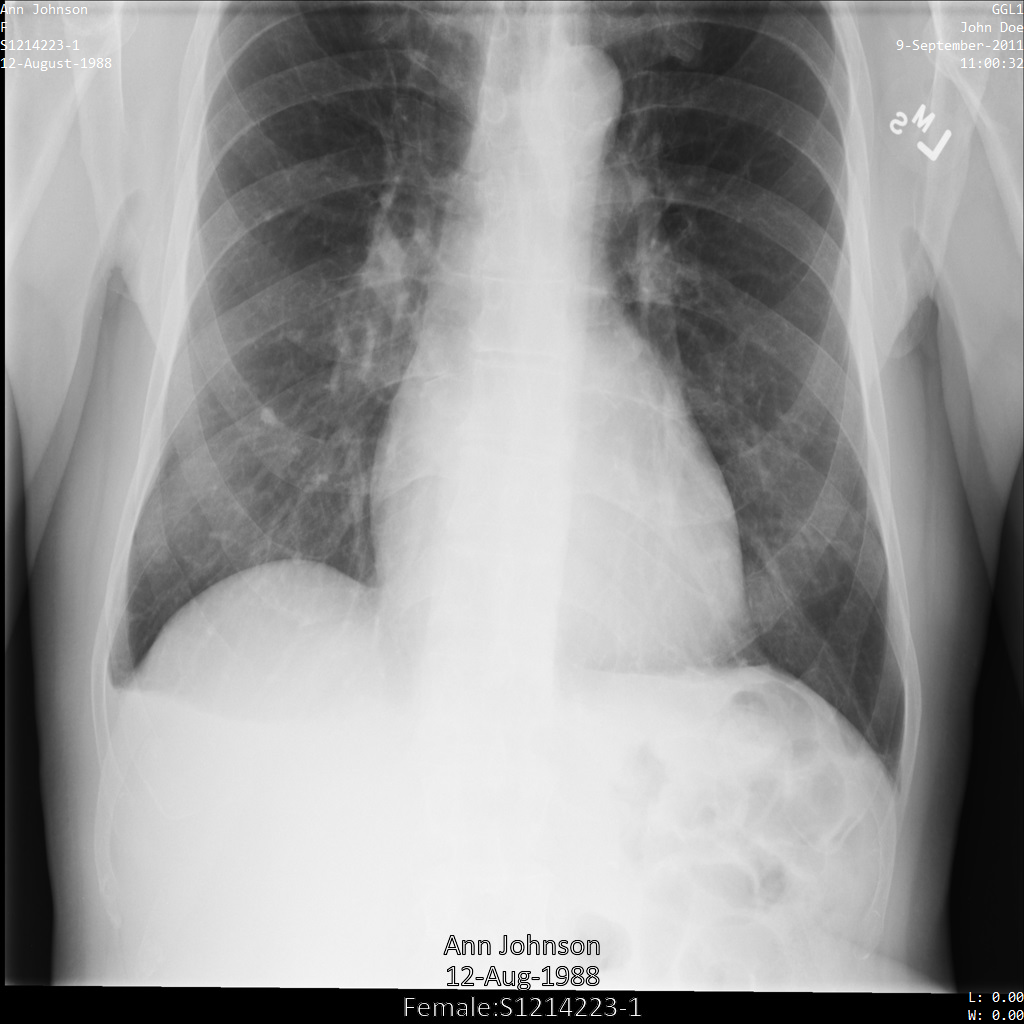

Contoh gambar

Beberapa contoh di halaman ini berisi output gambar yang tidak diidentifikasi. Setiap sampel menggunakan gambar asli berikut sebagai inputnya. Anda dapat membandingkan gambar output dari setiap operasi penghapusan identitas dengan gambar asli ini untuk melihat efek operasi: